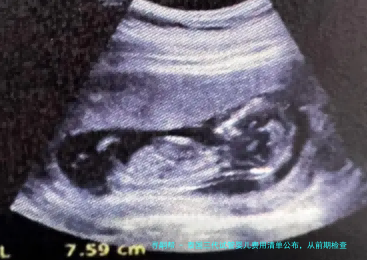

女性检查项目通常囊括:性激素六个项目(评估卵巢功能)、AMH(抗缪勒管激素,卵巢储备)、阴道B超(检查子宫、卵巢模样)、甲状腺功能、感染病筛查、染色体核型分析等。这一些检查的总花销大约在5000-8000人民币。